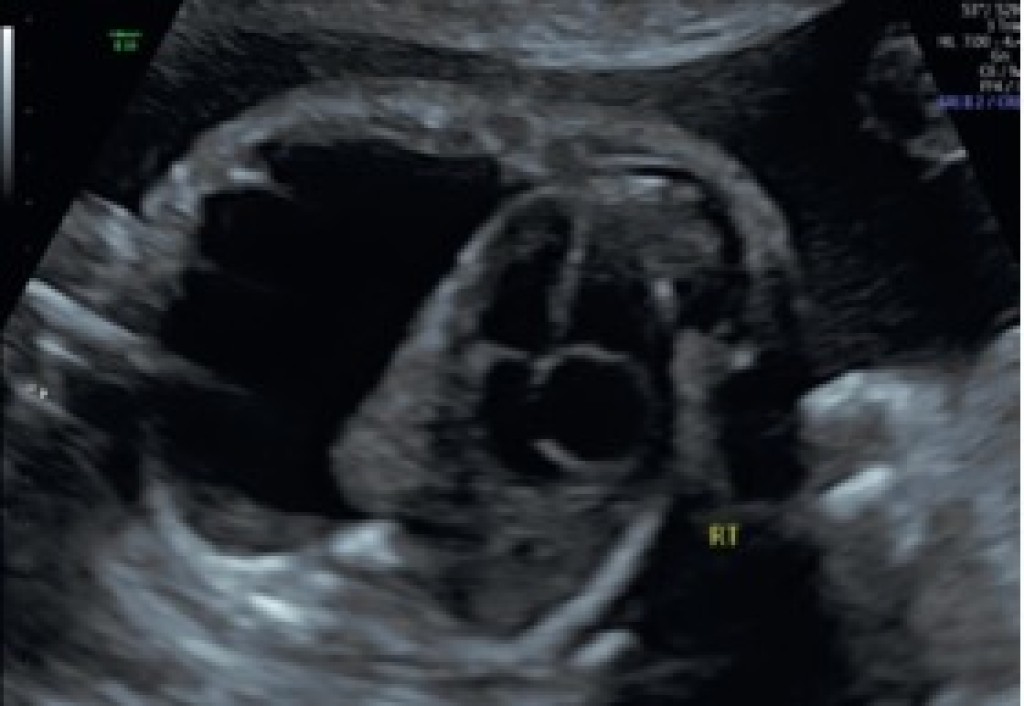

Fetal pleural effusion – before and after fetal intervention:

- Fetal thoracentesis – In this minimally invasive, ultrasound-guided procedure, a thin needle is placed through the mother’s uterus and into the fetal chest to draw out the fluid. During the procedure, a sample of chest fluid and amniotic fluid may be obtained for testing to help determine the cause of the pleural effusion and identify any other fetal conditions or abnormalities.

- Evaluate the fetal lungs for re-expansion, following thoracentesis.

- Watch for rapid buildup of fluid again – If the fluid quickly reaccumulates, determine if a shunt (drainage tube) would be beneficial to prevent repeated buildup, especially if it is early in the pregnancy.

- Thoracoamniotic shunting – Under ultrasound guidance, a small plastic tube, known as a shunt or catheter, is placed in the fetal chest, with one end in the chest cavity and the other end extending out into the amniotic cavity, enabling continual drainage of the pleural fluid. This is known as a “double pigtail catheter” (Rocket or Harrison shunt).

By draining the accumulated fluid, fetal interventions can reduce the pressure against the fetal lungs and heart, improving lung development, heart function and fetal outcomes.